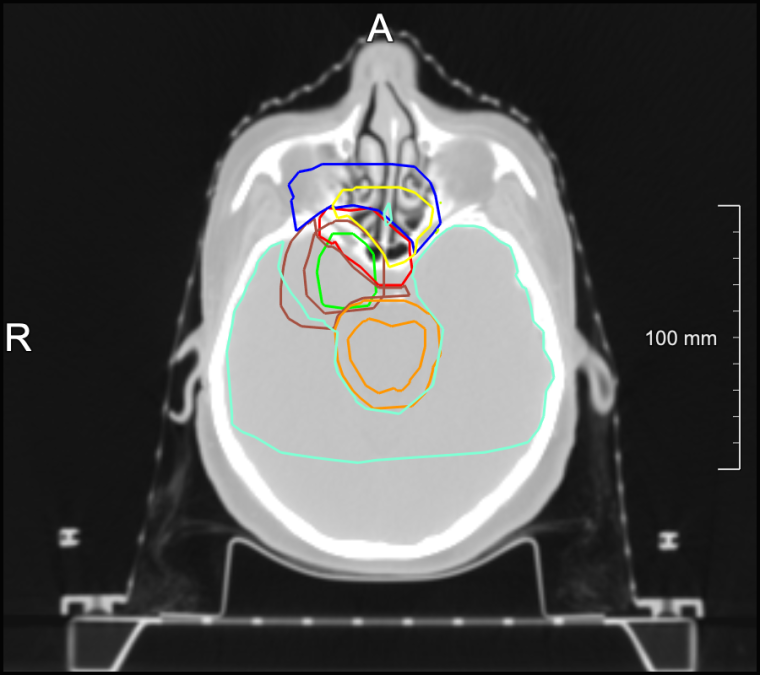

Aus Sicht der digitalen Bildverarbeitung ist die Konturierung von Objekten eine häufige Teilaufgabe und Voraussetzung für viele weitergehende Schritte zur Visualisierung, Vermessung oder genaueren Untersuchung. In der klinischen Praxis jedoch gibt es nur wenige Abläufe, in denen diese für Menschen langwierige und ermüdende Aufgabe wirklich durchgeführt wird; hierzu gehört die Bestrahlungsplanung. In den Schichtbildern einer dreidimensionalen Computertomographie werden dabei regelmäßig die zu bestrahlenden Zielstrukturen (Tumore) mit Sicherheitssäumen eingezeichnet, sowie Risikostrukturen, die geschont werden müssen. Dabei kommen in einem einzelnen Datensatz schnell hunderte von Konturen zusammen, was Zeit und Konzentration kostet. Ein Mensch muss dies zwar üben, aber geht meist nach festen Schemata vor, ohne sich intellektuell herausgefordert zu fühlen. Der Computer hingegen kann diese Aufgabe ohne Ermüdungserscheinungen, in immer gleicher Qualität und in wenigen Sekunden durchführen. Die künstlichen neuronalen Netze betrachten dabei auch nicht nur einzelne Schichten, wie sie am Bildschirm dargestellt und bearbeitet werden können, sondern haben keine Probleme mit einer direkten Analyse des dreidimensionalen Kontexts. Die Erfolge dieses Vorgehens haben früh das Interesse der Industrie geweckt, die in Kooperation mit Forschern z.B. des Fraunhofer-Instituts für Digitale Medizin MEVIS mittlerweile bereits an der Integration der ersten Modelle in Medizinprodukte arbeitet. Eine vollautomatische Konturierung kann bereits im Hintergrund in den IT-Systemen erfolgen, so dass die Ergebnisse sofort zusammen mit der Computertomographie dargestellt werden und niemand warten muss.

Deep Learning ermöglicht heute die vollautomatische Konturierung vieler Organe, Risikostrukturen oder sogar Tumore. Der Entwicklungsaufwand entsprechender Modelle ist trotz besserer Qualität dabei geringer als bei traditionellen Algorithmen, verlagert sich allerdings hin zu den Daten, die gesichtet, aussortiert, ggf. annotiert oder korrigiert werden müssen. Die in der klinischen Praxis unter Zeitdruck für die Bestrahlungsplanung eingezeichneten Konturen einer Risikostruktur wie der Niere eignen sich nicht automatisch für das Training eines neuronalen Netzes, denn um einen Tumor „an der Niere vorbei“ zu bestrahlen, ist Genauigkeit nur auf der dem Tumor zugewandten Seite wichtig. Menschliche Experten wissen und berücksichtigen dies, um Zeit zu sparen. Ein Computer hat dies nicht nötig, im Gegenteil; wenn man die so gezeichneten Konturen direkt dem maschinellen Lernen zuführt, verringert das die Qualität des entstehenden Modells. Bei der Entwicklung geeigneter Konturierungsmodelle und der Datenaufbereitung fließt daher sowohl medizinisches Fachwissen als auch Expertise über die KI-Technologien und ihre möglichen Fehlerquellen ein.